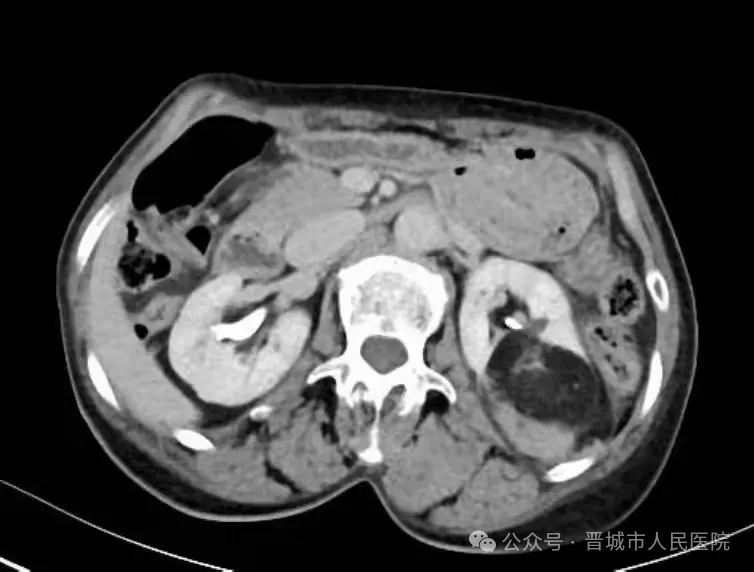

据了解,患者因体检发现左肾占位20余天入院,外院检查提示左肾肿物大小约45*55*98mm,接近十公分的肿瘤体积给治疗带来了极大挑战。更为棘手的是,患者年事已高,体质薄弱且营养状况欠佳,腹壁肌肉薄弱导致手术戳卡固定困难,传统腹腔镜手术操作空间受限、难度极高,而患者及家属保肾意愿十分强烈。

手术过程中,机器人系统的多自由度机械臂展现出独特优势,可灵活模拟人手动作,突破传统腹腔镜的操作角度限制,在狭小的术野内实现精细分离与操作。配合高清3D视野系统,术者能清晰辨识肾脏血管与肿瘤边界,精准把控手术节奏,有效规避血管损伤风险,为肿瘤完整切除和肾脏功能保留奠定了基础。